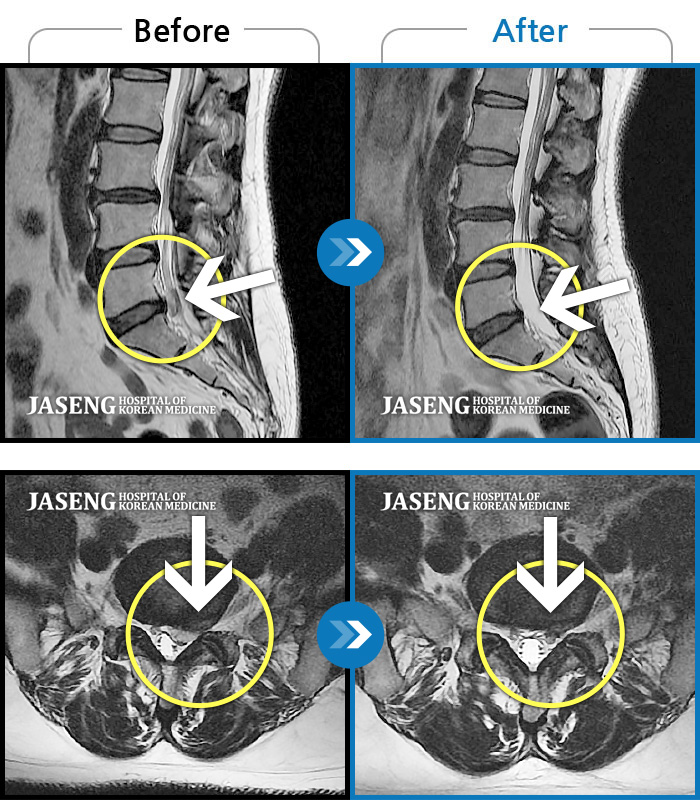

Before

After

환자에게 사전 동의를 받아 동일 조건에서 촬영되었습니다.

개인에 따라 치료 후 부작용이 발생할 수 있으니 의료진과 상담 후 치료를 진행하시기 바랍니다.

양측 하요추부~좌측 골반부 통증, 좌측 하지 전반적 비증 및 족저부 간헐적 비증